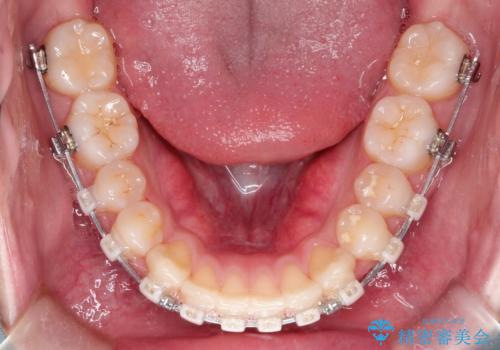

【クリア装置】前歯の凸凹を綺麗にしたい

- 矯正装置

- クリア装置

- 前歯の凸凹を主訴に来院されました。

マウスピース矯正も適応でしたが、ワイヤー矯正を希望され治療を行なっております